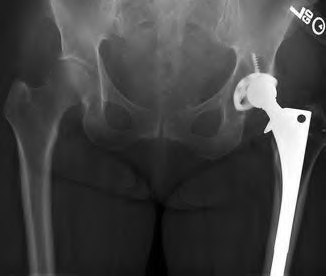

A 72-year-old female falls and sustains a periprosthetic femur fracture around her cementless total hip arthroplasty. Radiographs reveal a fracture extending just distal to the tip of the stem. The stem is radiographically loose, but there is excellent proximal and distal bone stock. According to the Vancouver classification, what is the fracture type and the recommended surgical treatment?

A 75-year-old female sustains a fall 5 years after a cementless THA. Radiographs show a periprosthetic femur fracture occurring around the stem tip. Intraoperative assessment reveals the stem remains firmly fixed in the metaphysis, and the proximal bone stock is adequate. According to the Vancouver classification, what is the fracture type and the standard recommended treatment?

A 78-year-old female sustains a periprosthetic femur fracture 10 years after a cemented THA. Radiographs show a fracture around the tip of the stem with a loose femoral component and poor proximal bone stock, but adequate diaphyseal bone.